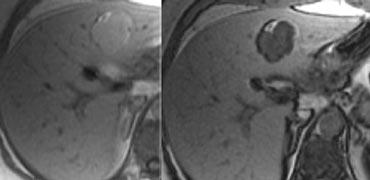

U máu khổng lồ có mô sẹo. Lưu ý mức độ ngấm thuốc tương đương hồ máu ở tất cả các thì. Sẹo trung tâm giảm tỷ trọng trên NECT và vẫn giảm tỷ trọng ở các thì sau.